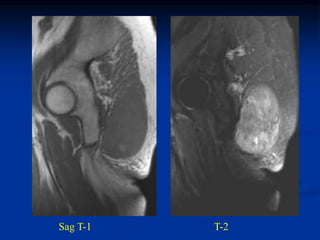

Case #1170.1              P.O. desmoid

61 year female with OA knee in 3/06 prior to TKA

Sag MRI 4/03

T-1                  T-2

MRI 1 year PO TKA

Sag T-2                       Gad

Axial

Gad

Surgical resection